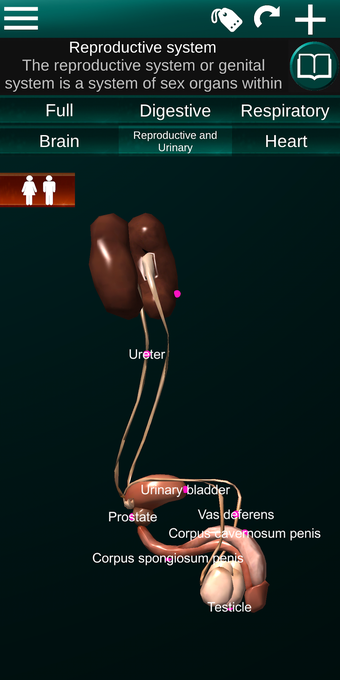

此应用程序显示人体器官的三维模型和所有器官的描述。

您可以触摸每个器官,如心脏、大脑、肺、生殖系统、肝脏、肠道、卵巢、睾丸、胃、肾脏等。

它对所有人都有用,甚至对学生也有用,因为每个解剖器官都以不同的颜色显示。